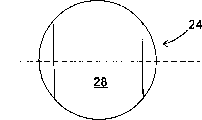

Family Cites Families (57)